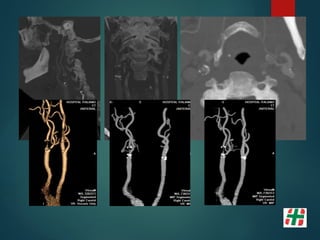

Paciente mujer 56 años, fumadora.

Episodios repetidos de déficit

transitorios en ambos hemicuerpo,

mayormente del lado derecho.

Paciente mujer 56años, fumadora. Episodios repetidos de déficit transitorios en ambos hemicuerpo, mayormente del lado derecho.